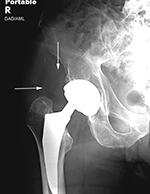

| Right hip dislocation with displaced polyethylene liner |

| Initial AP radiograph (left) shows a right hip dislocation. Note the polyethylene liner (arrow) is still associated with dislocated femoral head. The hip was subsequently relocated. The AP radiograph (middle) show subtle eccentric positioning of the reduced femoral head within the acetabular cup. A subtle density (arrows) represents the liner which is now disassociated from the femoral head. This is somewhat more clearly shown (arrow) on the frog leg lateral view (right). |